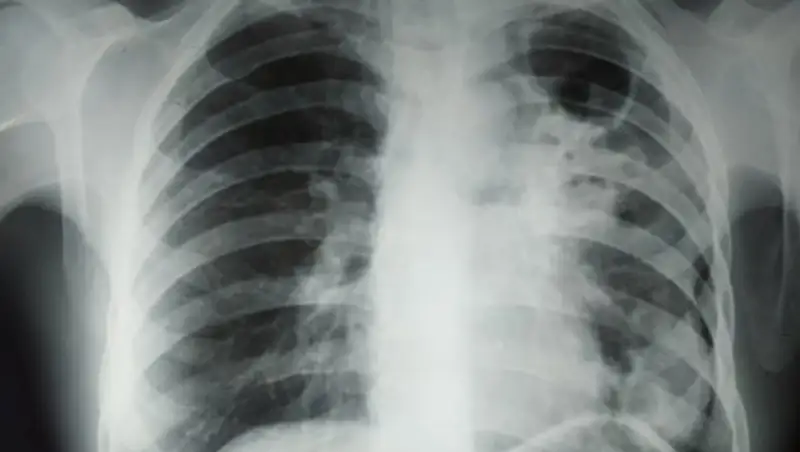

ВОЗ признает туберкулез "самой заразной смертоносной болезнью", учитывая, что этим недугом каждый год заражаются 10 млн человек при смертности 1,5 млн за то же время. Туберкулез вызывается бактерией, и эта болезнь, как правило, затрагивает легкие. Тем не менее это заболевание лечится антибиотиками. Учитывая наличие эффективных средств лечения, главный метод борьбы с туберкулезом — это тестирование и охват как можно большего количества людей.